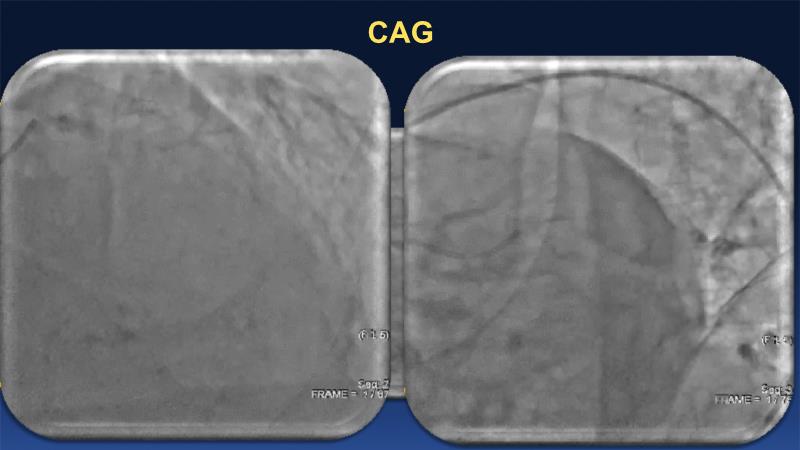

Over the last five years, we have learned that there is a new tool for treating calcium, the greatest enemy of interventional cardiology, which can take various forms: intravascular lithotripsy. In this session, look at how to master this technique in different scenarios, from eccentric calcified lesions to left main bifurcations.

- To learn how to safely utilise IVL in left main bifurcations